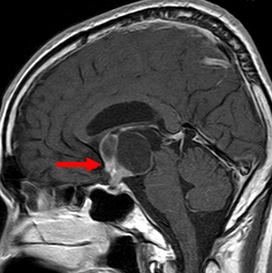

当院での症例をお示しします。症例は66才女性、進行する左眼の視力(左:手動弁)、視野障害にて当院来院。MRIにて赤矢印のように左蝶形骨内側に大きな腫瘍を認めます。開頭手術治療前に腫瘍の栄養血管にカテーテルを入れて、固体塞栓物質を造影剤と混ぜて注入します。最後に再開通しない様プラチナコイルを留置して終了します。その2日後に腫瘍摘出を行いましたが、出血は少量で輸血も行っておりません。視力も左は1.5まで改善し、患者さんは元気で退院しました。(図1-a・b、図2-a・b、図3-a・b、図4-a・b)

図1-a:術前 |